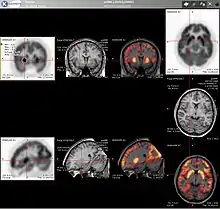

PET imaging with 18F-FDG takes advantage of the fact that the brain is normally a rapid user of glucose. Standard 18F-FDG PET of the brain measures regional glucose use and can be used in neuropathological diagnosis.

Brain pathologies such as Alzheimer's disease greatly decrease brain metabolism of both glucose and oxygen in tandem. Therefore 18F-FDG PET of the brain may also be used to successfully differentiate Alzheimer's disease from other dementing processes, and also to make early diagnoses of Alzheimer's disease. The advantage of 18F-FDG PET for these uses is its much wider availability. Some 18F based radioactive tracers used for Alzheimer's include florbetapir, flutemetamol, PiB and florbetaben, which are all used to detect amyloid-beta plaques (a potential biomarker for Alzheimer's) in the brain.[17]

PET imaging with FDG can also be used for localization of seizure focus. A seizure focus will appear as hypometabolic during an interictal scan.[18] Several radiotracers (i.e. radioligands) have been developed for PET that are ligands for specific neuroreceptor subtypes such as [11C] raclopride, [18F] fallypride and [18F] desmethoxyfallypride for dopamine D2/D3 receptors, [11C] McN 5652 and [11C] DASB for serotonin transporters, [18F] Mefway for serotonin 5HT1A receptors, [18F] Nifene for nicotinic acetylcholine receptors or enzyme substrates (e.g. 6-FDOPA for the AADC enzyme). These agents permit the visualization of neuroreceptor pools in the context of a plurality of neuropsychiatric and neurologic illnesses.